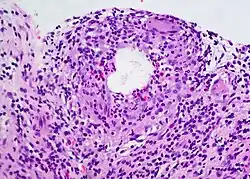

Classic lipogranulomatous response seen in a well-developed chalazion